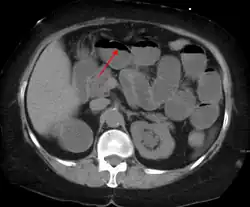

The main diagnostic tools are blood tests, X-rays of the abdomen, CT scanning, and ultrasound. If a mass is identified, biopsy may determine the nature of the mass.

Radiological signs of bowel obstruction include bowel distension (small bowel loops dilated >3 cm) and the presence of multiple (more than 2) air-fluid levels on supine and erect abdominal radiographs.[16] Ultrasounds may be as useful as CT scanning to make the diagnosis.[17]

Contrast enema or small bowel series or CT scan can be used to define the level of obstruction, whether the obstruction is partial or complete, and to help define the cause of the obstruction. The appearance of water-soluble contrast in the cecum on an abdominal radiograph within 24 hours of it being given by mouth predicts resolution of an adhesive small bowel obstruction with sensitivity of 97% and specificity of 96%.[18]